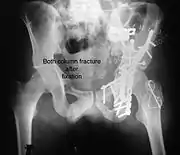

Both column fracture after fixation with screws and plates

The final management depends on the size of the fragment(s), stability and congruence of the joint. In some cases traction for six to eight weeks may be the only treatment required; however, surgical fixation using screw(s) and plate(s) may be required if the injury is more complex. The latter treatment will be called for if bone fragments do not fall into place, or if they are found in the joint, or if the joint itself is unstable.

- Anatomic reduction of the fractured fragments

- Stable fixation

- Congruent joint

- Early mobilization

- Delayed weight bearing

Innominate bone is a flat bone with many curves. In most part the bone is thick enough and has broad surfaces that are amenable to primary fixation using lag screw(s) and to neutralize forces across the bone one needs to add plate(s) on the surface of the fractured fragments for it to heal without deformity.